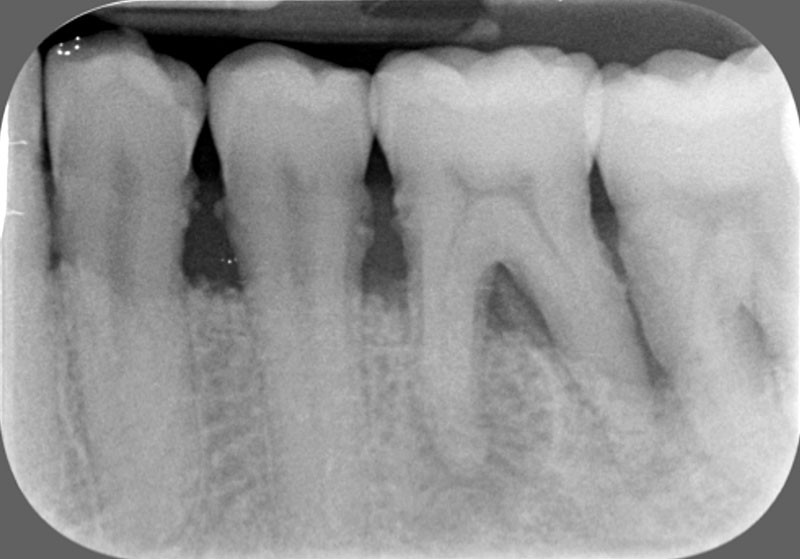

sondage parodontal à l’aide d’une sonde graduée (fig. 3) de tout le quadrant d’arcade;